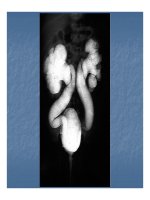

KHÁM LÂM SÀNG HỆ THỐNG SINH DỤC TIẾT NIỆU

Khám lâm sàng hệ thống sinh dục tiết niệu gồm có:

Khám thận, niệu quản,bàng quang, niệu đạo,ở đàn

ông có them tuyền liệt tuyến nằm ở vùng cổ bàng quang.

I.Khám hệ thống thận tiết niệu

I/Cách khám thận